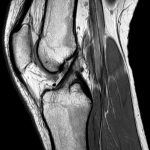

Giải phẫu MRI khớp gối.

Axial / Coronal / Sagittal